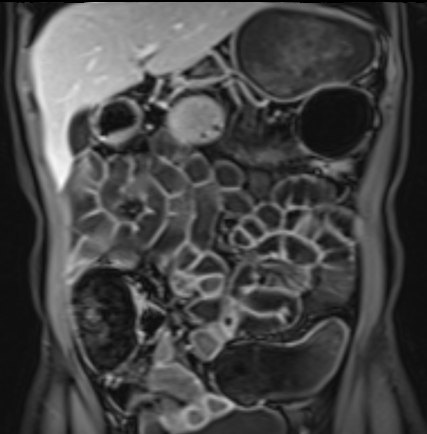

Bệnh nhân nữ 48 tuổi, đang điều trị bằng thuốc kháng TNF, được chỉ định nội soi đại tràng.

Phát hiện hẹp lòng ruột ở đại tràng sigma, không thể vượt qua được khi nội soi.

MR-enterography được thực hiện để đánh giá mức độ lan rộng của chỗ hẹp.

Cuộn qua các hình ảnh.

Ruột non bình thường, nhưng ghi nhận các đoạn hẹp ở đại tràng xuống và đại tràng ngang.

Cả hai đoạn hẹp đều có thành ruột dày đến 8 mm và ngấm thuốc rõ rệt theo kiểu niêm mạc ở đại tràng xuống và kiểu phân lớp ở đại tràng ngang.

Giãn ruột trước chỗ hẹp được ghi nhận ở cả hai đoạn.

Do các chỗ hẹp này không hiện diện khi nội soi đại tràng trước khi điều trị kháng TNF, nhiều khả năng chúng đã hình thành trong quá trình điều trị.

Do đó, quyết định phẫu thuật cắt đại tràng gần toàn bộ với miệng nối hồi-sigma đã được đưa ra.